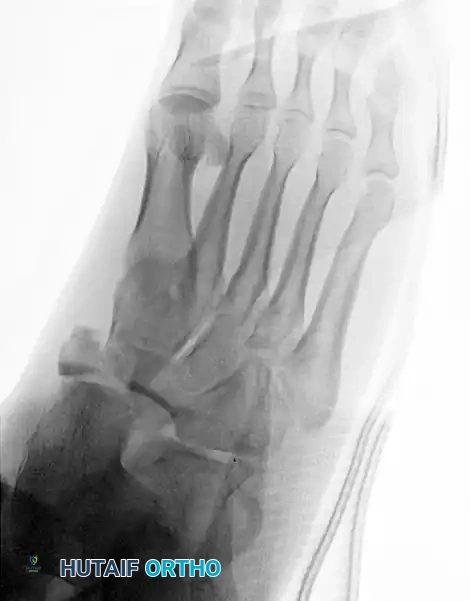

Clinical Evaluation and Radiographic Parameters

Any injury resulting in midfoot tenderness, swelling, or an inability to bear weight merits rigorous evaluation.

Radiographic Evaluation:

Standard non-weight-bearing radiographs often miss subtle instability. Weight-bearing radiographs are absolute requirements if the patient can tolerate them. If the patient cannot bear weight, a short-leg cast should be applied for 10-14 days, followed by repeat weight-bearing films.

Key radiographic parameters to evaluate:

1. The medial shaft of the 2nd metatarsal must align perfectly with the medial aspect of the middle cuneiform on the AP view.

2. The medial shaft of the 4th metatarsal must align perfectly with the medial aspect of the cuboid on the oblique view.

3. The 1st metatarsal-cuneiform articulation must show no incongruency.

4. The "Fleck Sign": Look for a small bony avulsion in the space between the medial cuneiform and the base of the 2nd metatarsal. This represents a bony avulsion of the Lisfranc ligament.

5. Evaluate the naviculocuneiform articulation for subtle subluxation.

If plain radiographs are equivocal but clinical suspicion remains high, CT imaging is excellent for identifying occult fractures, while MRI is the gold standard for evaluating the integrity of the Lisfranc ligament complex.